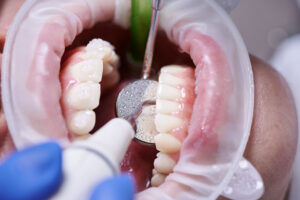

Dental implants have many components. Find out how to get a transparent dental implant cost package.

You might require bone graft under some circumstances to ensure a strong and long-lasting implant procedure.

Dental implants can be partially financed with Medisave or dental insurance. Find a financing plan for you.